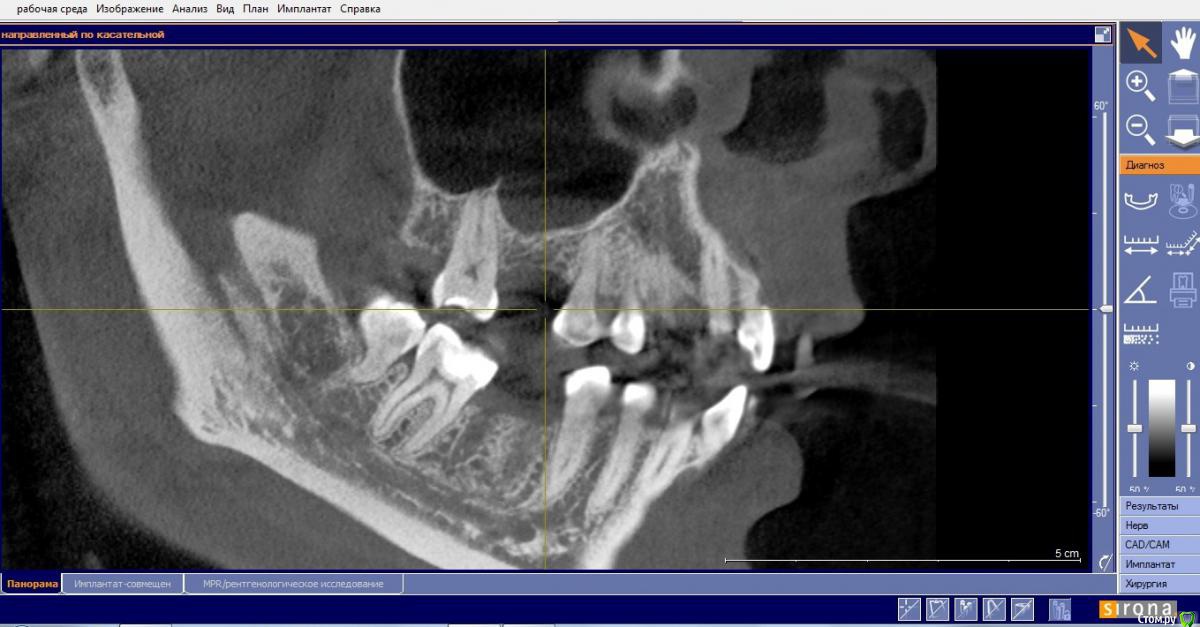

Маргарита19 Опубликовано 2 апреля, 2016 Автор Поделиться Опубликовано 2 апреля, 2016 Не совсем, но похоже можно закрытым синуслифтом обойтись. Скрин области интереса нужен в щечно - небной плоскость, а Вы выкладываете реконструкцию панорамы.Не могу справиться с компом, перестал показывать 3Д, только панорама и все... Я так понимаю КТ целое от сироны скачивать никто не будет или можно рискнуть и разместить ссылку? Ссылка на комментарий

red_butler Опубликовано 2 апреля, 2016 Поделиться Опубликовано 2 апреля, 2016 Не могу справиться с компом, перестал показывать 3Д, только панорама и все... Я так понимаю КТ целое от сироны скачивать никто не будет или можно рискнуть и разместить ссылку?Может кто и скачает. Я качаю только когда с рабочего ноута выхожу. Телефон физически не позволяет этого сделать. Ссылка на комментарий